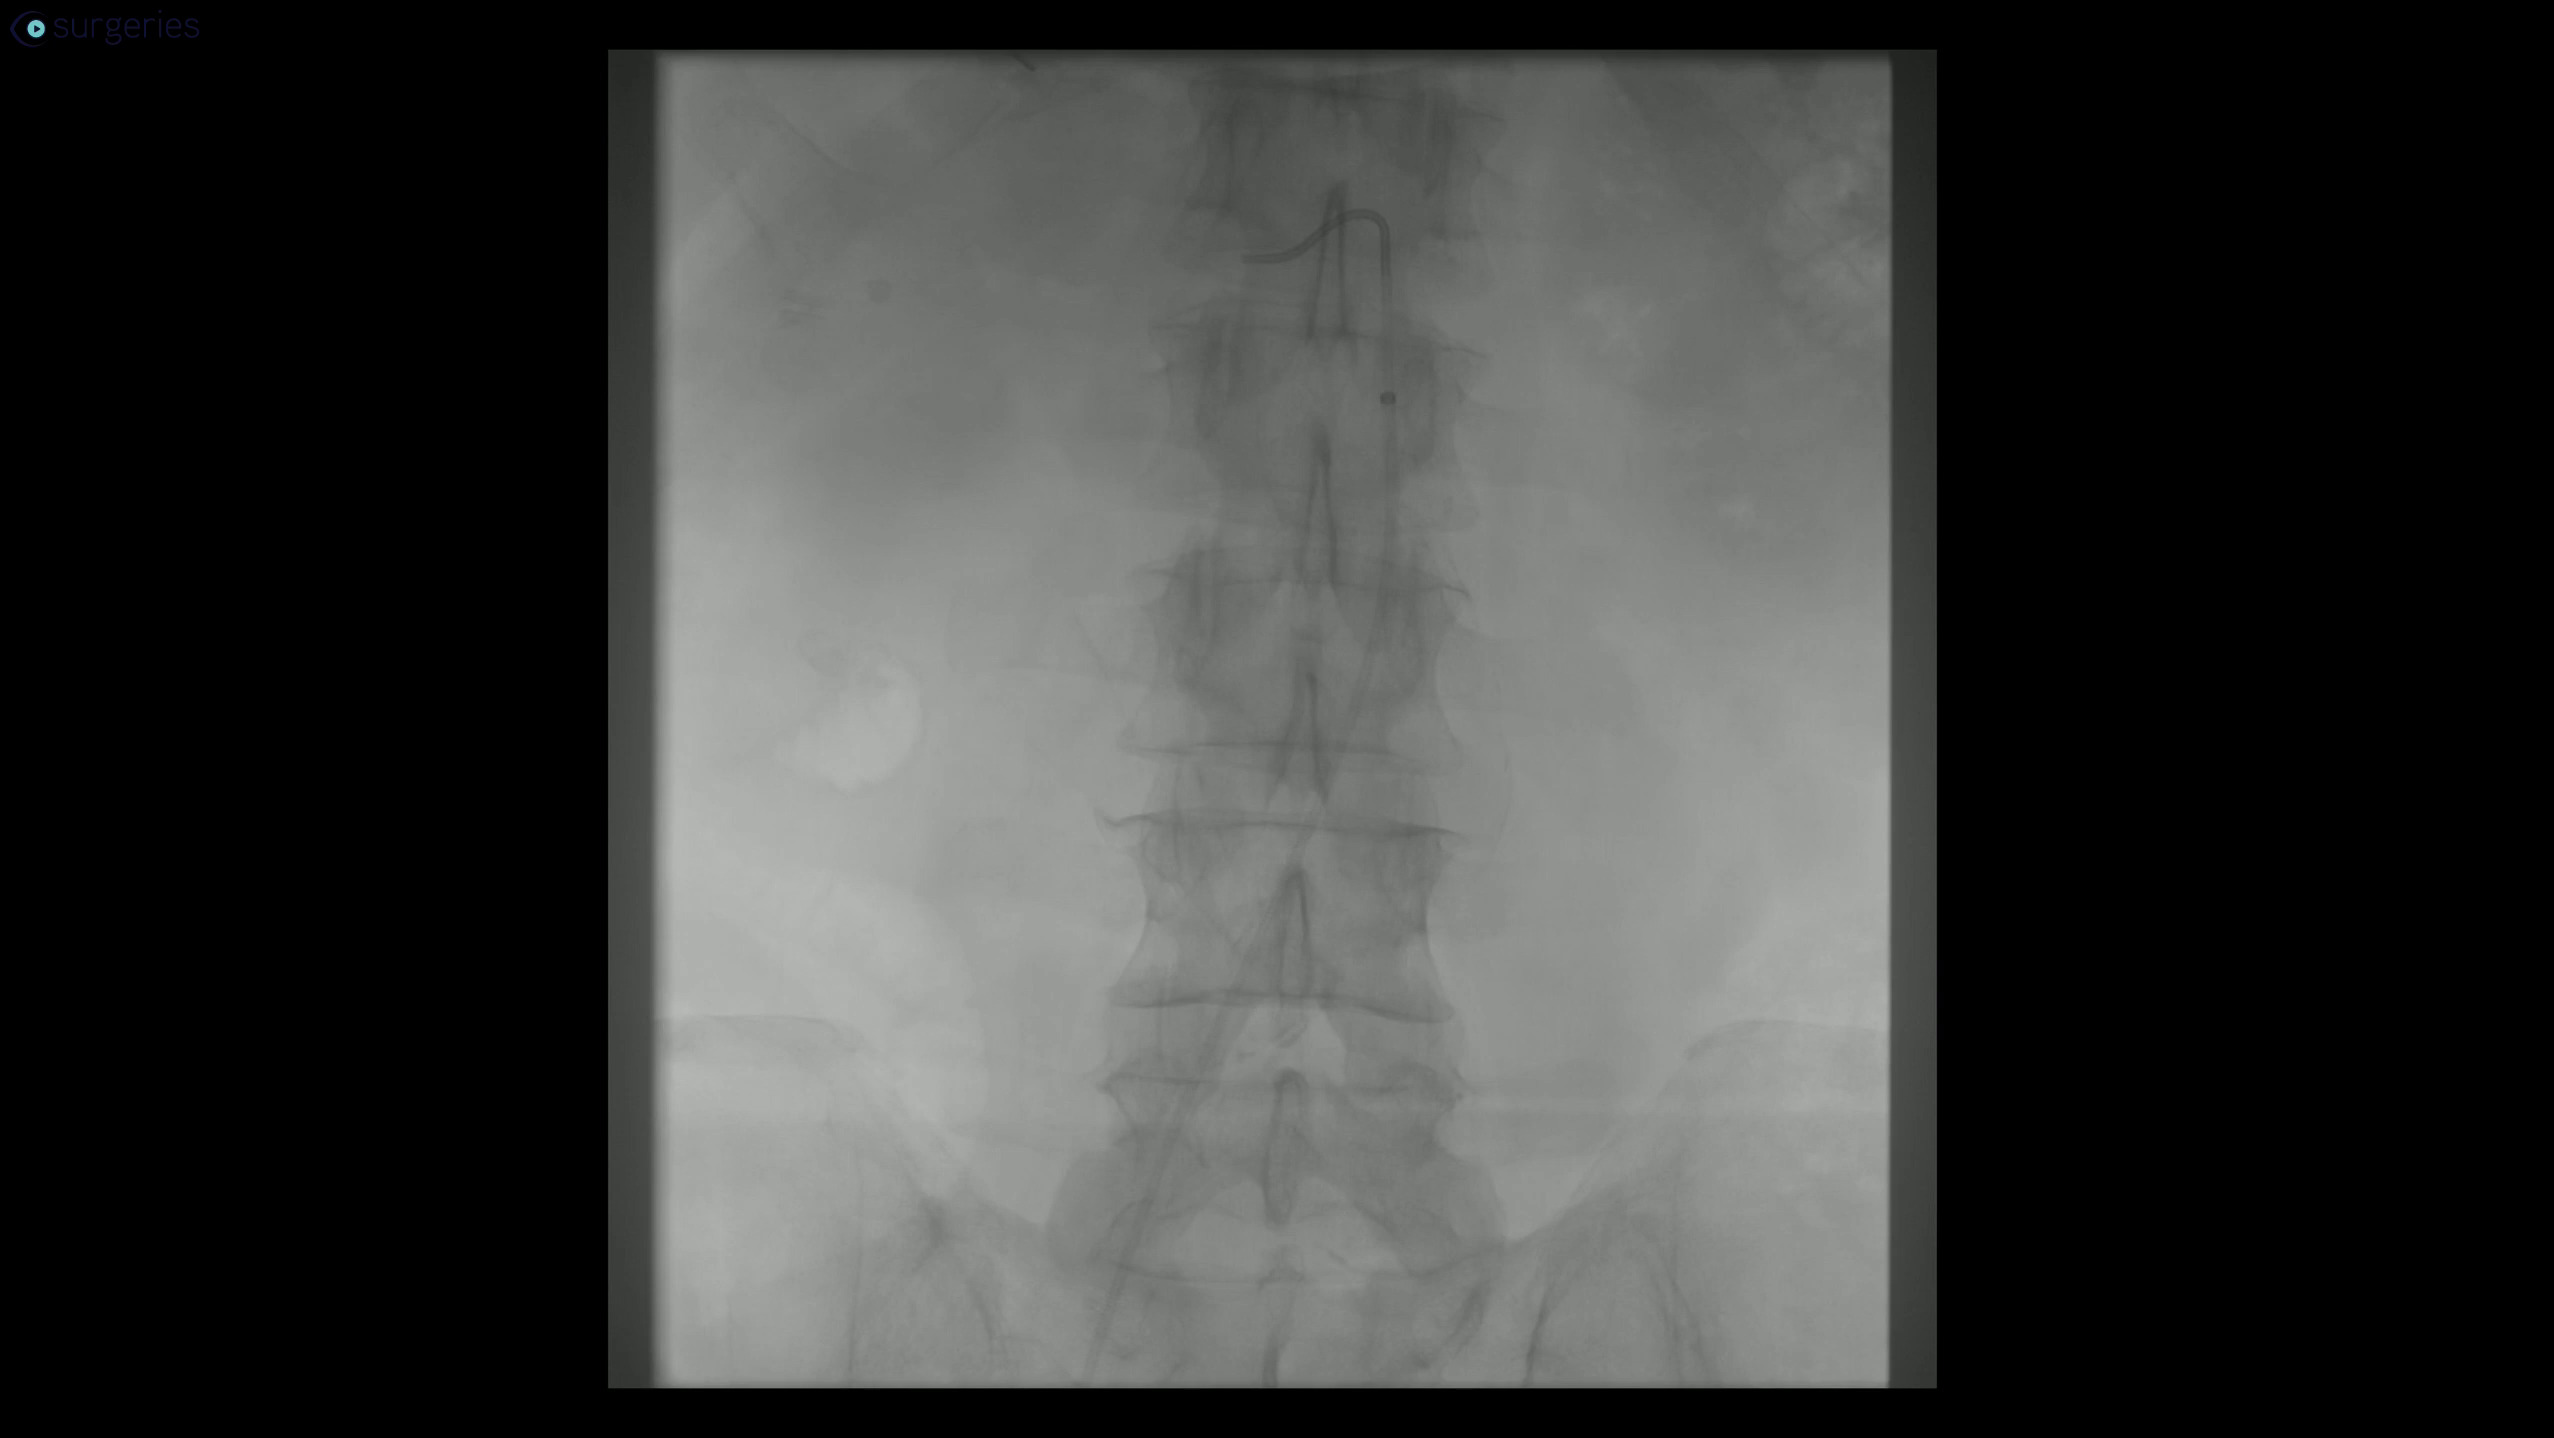

Watch the Full VideoDouble-chambered right ventricle repair for an adolescent male who presented with a subaortic perimembranous ventricular septal defect, a subaortic membrane with associated left ventricular outflow tract obstruction, and a double-chambered right ventricle. This video highlights a VSD patch closure and the surgical resection of the subaortic membrane and RVOT muscle bundles.